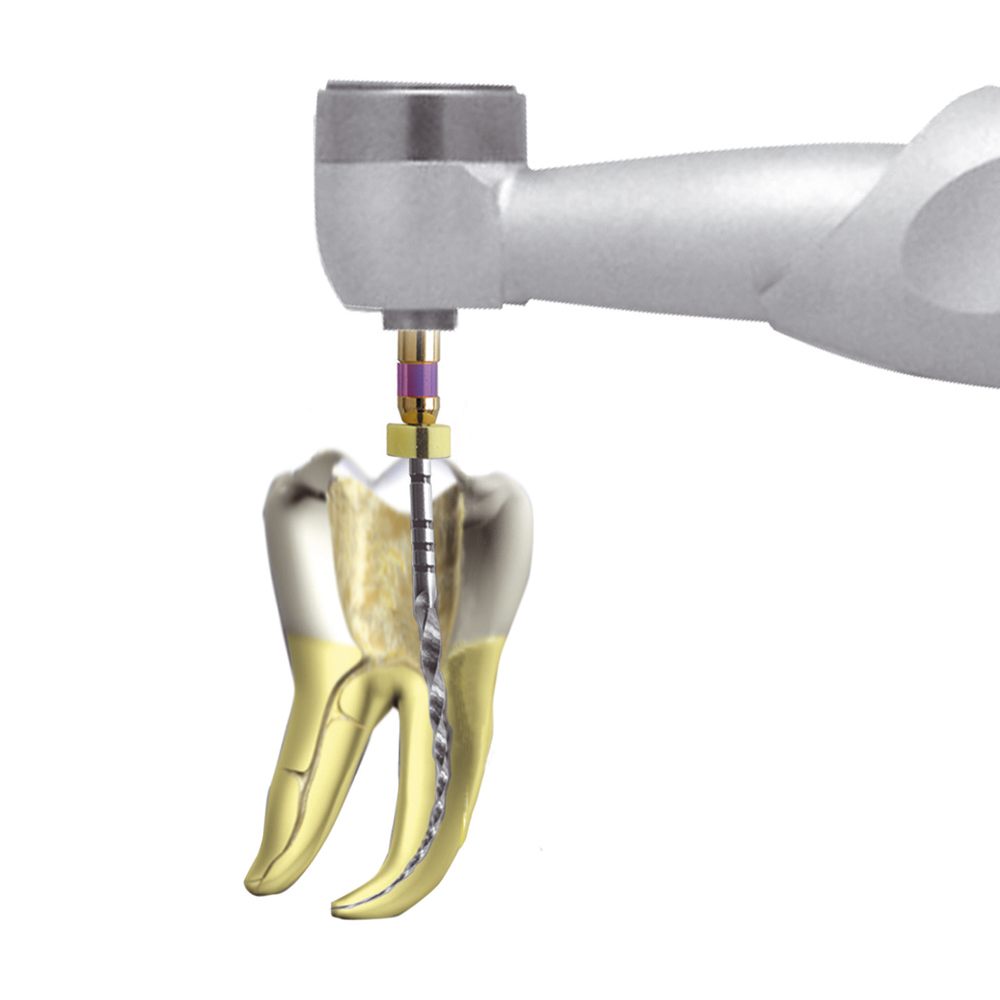

Le traitement de canal, ou traitement endodontique, est nécessaire quand la pulpe de la dent est infectée suite à une carie importante, des fissures à l’émail ou un traumatisme (choc).

Ce traitement consiste donc à enlever la pulpe infectée des canaux où elle loge, à désinfecter tout le système de canaux de la dent, à élargir le canal principal et à obturer le réseau canalaire (le remplir et le sceller).

Le nettoyage de l’intérieur de la dent utilise la combinaison d’une méthode mécanique (des limes qui grattent et enlèvent les débris à l’intérieur des canaux) et d’une méthode chimique (solution de désinfection injectée dans la dent pour tuer les bactéries).

Pour retirer la pulpe des canaux de la dent (méthode mécanique), le dentiste se sert d’instruments de précisions (petites limes).

Ces instruments peuvent être utilisés manuellement ou être mécanisés (activés par un moteur électrique).